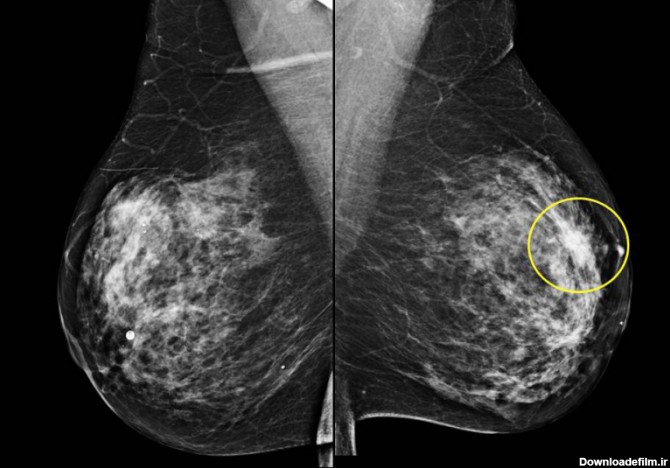

ماموگرافی یا ماموگرام، تصویر اشعه ایکس از پستان می باشد تا موارد سرطان پستان را غربالگری کند. ماموگرافیها نقش مهمی در تشخیص زودهنگام سرطان بازی میکنند و به کاهش مرگ و میرهای ناشی از سرطان سینه کمک میکنند.

ماموگرافی یکی از راههای تشخیص سرطان پستان در زنان می باشد که منجر به کشف سرطان در مراحل اولیه می شود. در این مطلب، به چیستی و چگونگی ماموگرافی خواهیم پرداخت.

ماموگرافی، تصویربرادی از سینه و از مهمترین ارکان تشخیص سرطان سینه یا هر بیماری سینه است. این سرطان بین خانمها شایع است و باید مرتب سلامت سینه را چک کرد.